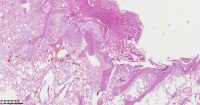

请教老师们这些巨细胞有什么临床意义?

性别

女

年龄

61岁

临床诊断

股骨头骨折

一般病史

标本名称

股骨头组织

大体所见

股骨头骨折处组织

多核吞噬细胞,有纤维素性坏死

是一种反应性改变。